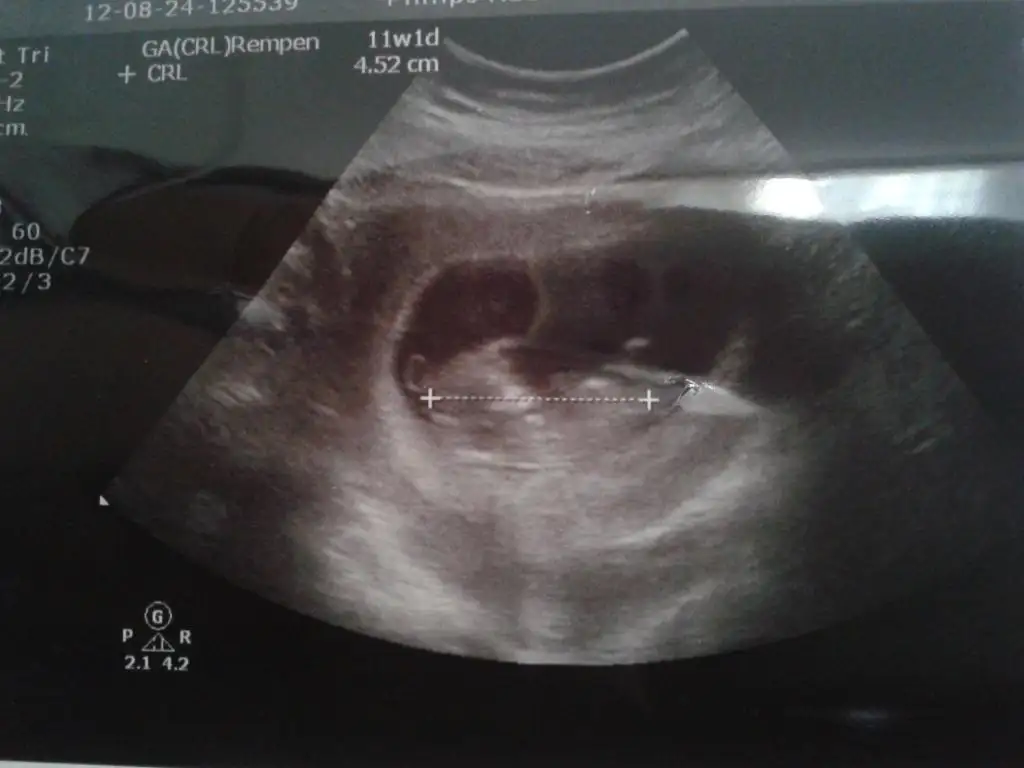

dr soylemeden siz gorun genital nub teorisi ( bebegin cinsiyeti)

orkidem bide bu ayrıntılı ultrason resmi :) gıcık oldum doktora yaaaa sinir etti beni kızda olabilir erkekte olabilir diyooo ben ikisinede razıyım ama insan ona göre kıyafet bakıp mutlu olmak istiyo işin yoksa habire bi kız bi erkek şeylerine bak sence ben hangi renk kıyafetler bakmalıyım orkidemmm nolur kesin konuşşşş bayram bayram sevinçli geçsin

yukari dogru olan bacaklari bence bide 12 haftalikken koy bakalim o zaman daha belirgin oluyo

herkese merhaba arkadaslar, bu nub teorisi 13.ve 14. haftada yuzde doksana varan dogru tahminlerde bulunuluyor ama ozellikle 13. hafta beklenmeliymis cunku 12'den sonra penis aci vermeye baslarmis. tek yanilma noktasi omrume de oldugu gb erkegin de kiz nubunda oldugu gb paralel durabilcegi, bu da 14.haftda tamamen degismis olurmus. yani aci yuzde otuz ve daha fazla veriyorsa kesin erkek bu hic degismiyor ama kiz denilen belki yanilabiliyor. birazdan ben de resim ekleyecegim fikrinizi almak istedim:)

kizlar benim icin de yorumda bulunabilirmisiniz, dokor yuzde 70 erkek dedi ama boyu cok uzun oldugu icin bu kadar uzun kiz olmaz dedi. 12+2 de gittim uc gun de ileride gorunuyordu?

cok tesekkur ederim orkide ayrica bu konuyu bulup hepimize ogrettigin icin de cok tesekkur ederim. cok sasirdim bu basliga ilginin bu kadar az olmasina; yabanci sitelerde kimse cin takvimi vs takmiyor ama herkes nub teorisini konusuyor. bence kadinlar kulubunde bu konu henuz yeterince okunmadi yoksa burda yuzlerce resim olurdu. doktorun boyuna gore bu denli net konusmasina ben de cok sasirdim sonucta babasi 180 oglum da yasitlarina gore uzun, amcasi dayisi zaten 185ler. daha yeni bir yabanci steye bu resmi koydum hep erkek tahmin ettiler cunku resimdeki havaya kalkan bacagi nub diye yorumladilar. gobege dogru gordugum cok net cikmayan ince sekil nub degil mi? ve oldukca paralel beline.